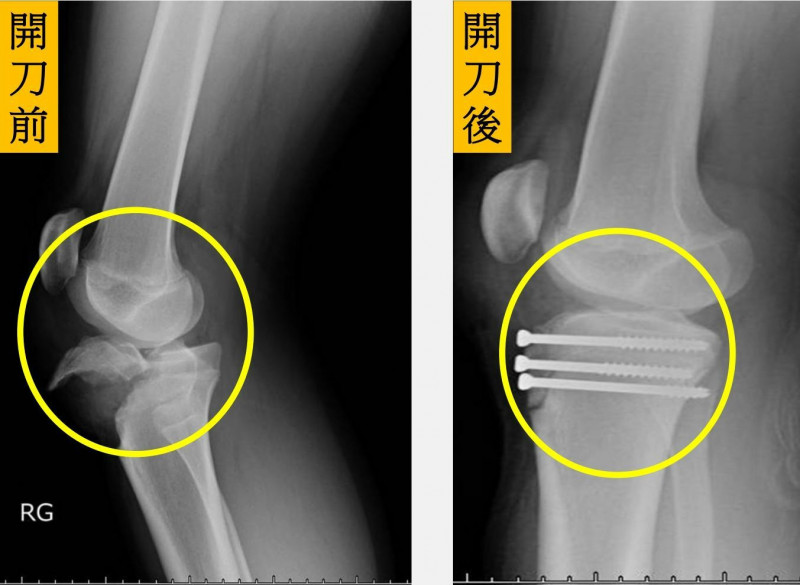

〔記者陳建志/台中報導〕15歲的林小弟熱愛籃球,某天在球場帥氣奔馳切入跳投後,落地瞬間整個右膝蓋感到劇烈疼痛,無法伸直及站立,老師趕緊將他送醫,經X光檢查發現右腳膝蓋的近端脛骨出現骨折,連帶生長板也受傷,所幸骨科醫師為他安排骨折復位固定手術後,3天就出院,經3個月追蹤,骨折已癒合且恢復肌肉力量,順利重返球場。

李祥安指出,此類骨折的治療選擇包含保守治療以及手術治療。當骨折碎片沒有位移時,可以考慮採取石膏固定維持膝關節伸直約4週的時間。當骨折有明顯位移,尤其是骨折有裂到膝關節裡面時,藉由手術來將關節面恢復平整是必要的。至於骨材的選擇可根據患者的年齡而定,若小於10歲生長板尚未閉合的兒童,建議使用平滑鋼針固定避免破壞生長板,若為青少年、骨齡將近成熟的病人,則可以使用螺釘固定,固定效果更強。